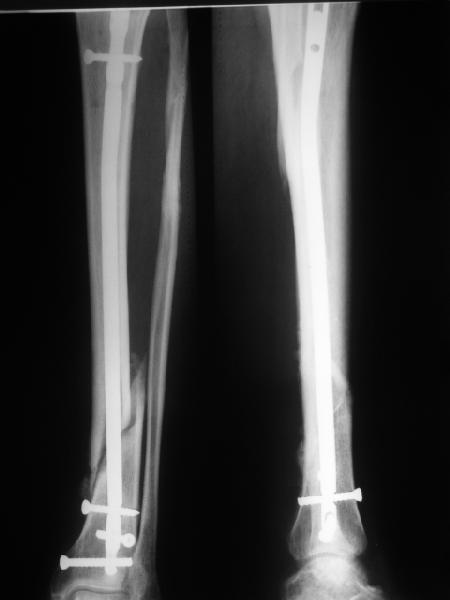

>СА> представленные снимки этому подтверждение-данный кососпиральный

СА> перелом репонируется идеально только открыто,что при БИОС не так существенно.

Здесь проблема не в идеальности репозиции, а в запасе усталостной прочности. Срастаться там может небыстро, диастазы довольно большие.

И когда еще и отломок короткий, и отверстие совсем рядом, это может привести к перелому стержня. За последние годы у нас было несколько пациентов, оперированных в других учреждениях с

подобным положением отломков, с такими переломами гвздей. И сейчас переделать куда как проще и легче, чем иметь дело со сломанным гвоздем.

Антон, дорогой, важнее вальгуса тут близость верхнего отверстия к перелому и отсутствие уверенности в быстром сращении из-за большого

диастаза.